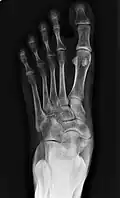

Radiographie du pied montrant un os naviculaire accessoire | ||

Un os naviculaire accessoire est un os accessoire du pied qui se développe parfois anormalement devant la cheville vers l'intérieur du pied. Cet os peut être présent dans environ 2 à 14 % de la population générale et est généralement asymptomatique[1],[2],[3]. Lorsqu'il est symptomatique, une intervention chirurgicale peut être nécessaire.

Les radiographies sont généralement commandées pour confirmer le diagnostic. S'il y a une douleur ou une inflammation en cours, une IRM ou d'autres tests d'imagerie avancés peuvent être utilisés pour évaluer davantage la condition.

Images radiologiques

De gauche à droite : types 1, 2 et 3